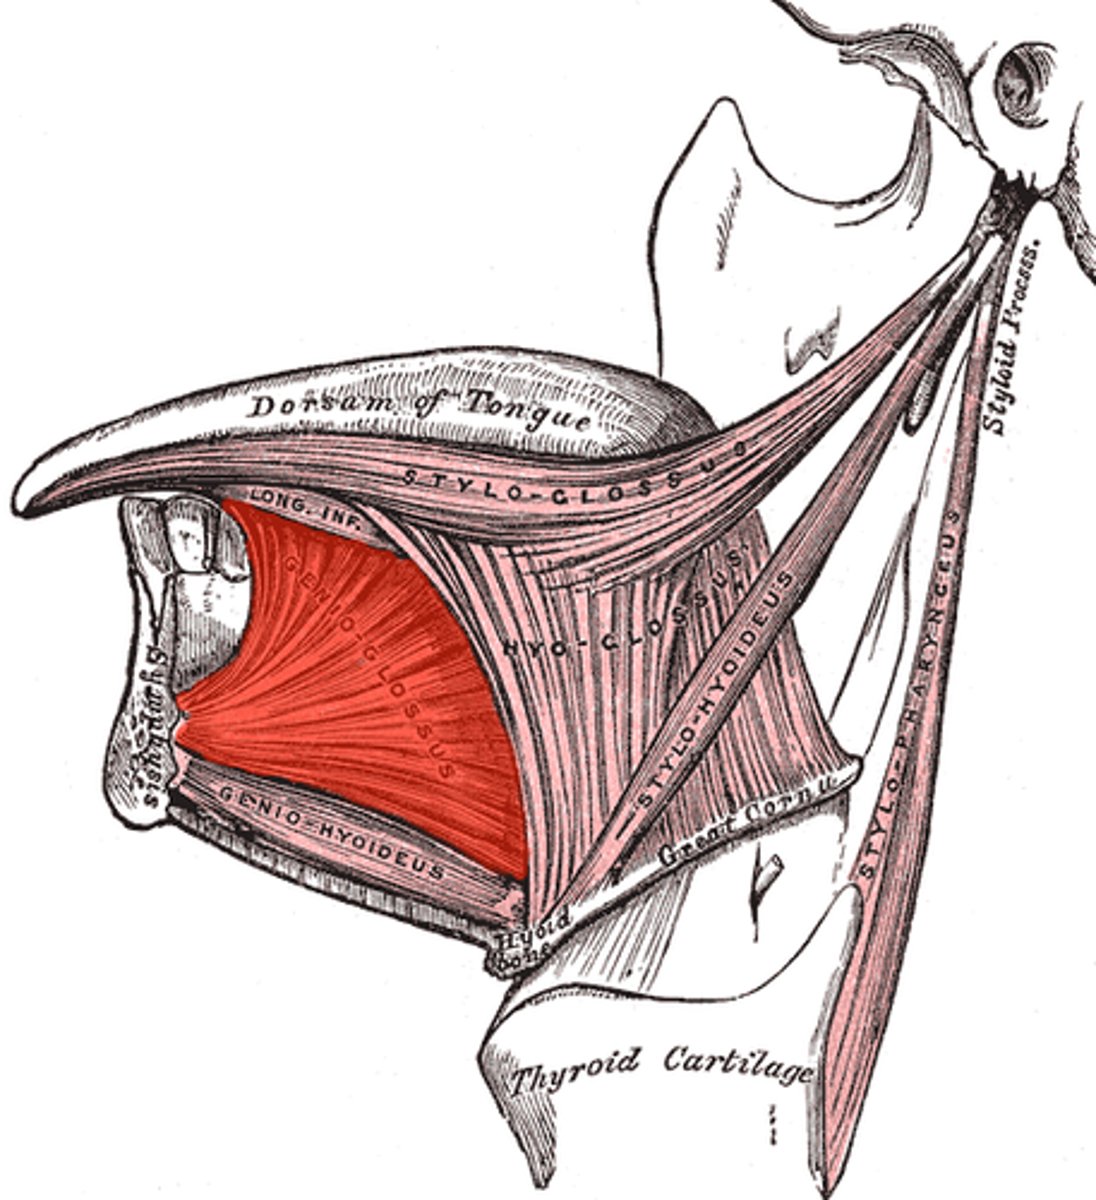

genioglossus

geniohyoid

lingual nerve

lingual artery

lingual vein

lingual nerve

genioglossus

geniohyoid

mylohyoid

lingual artery

lingual nerve